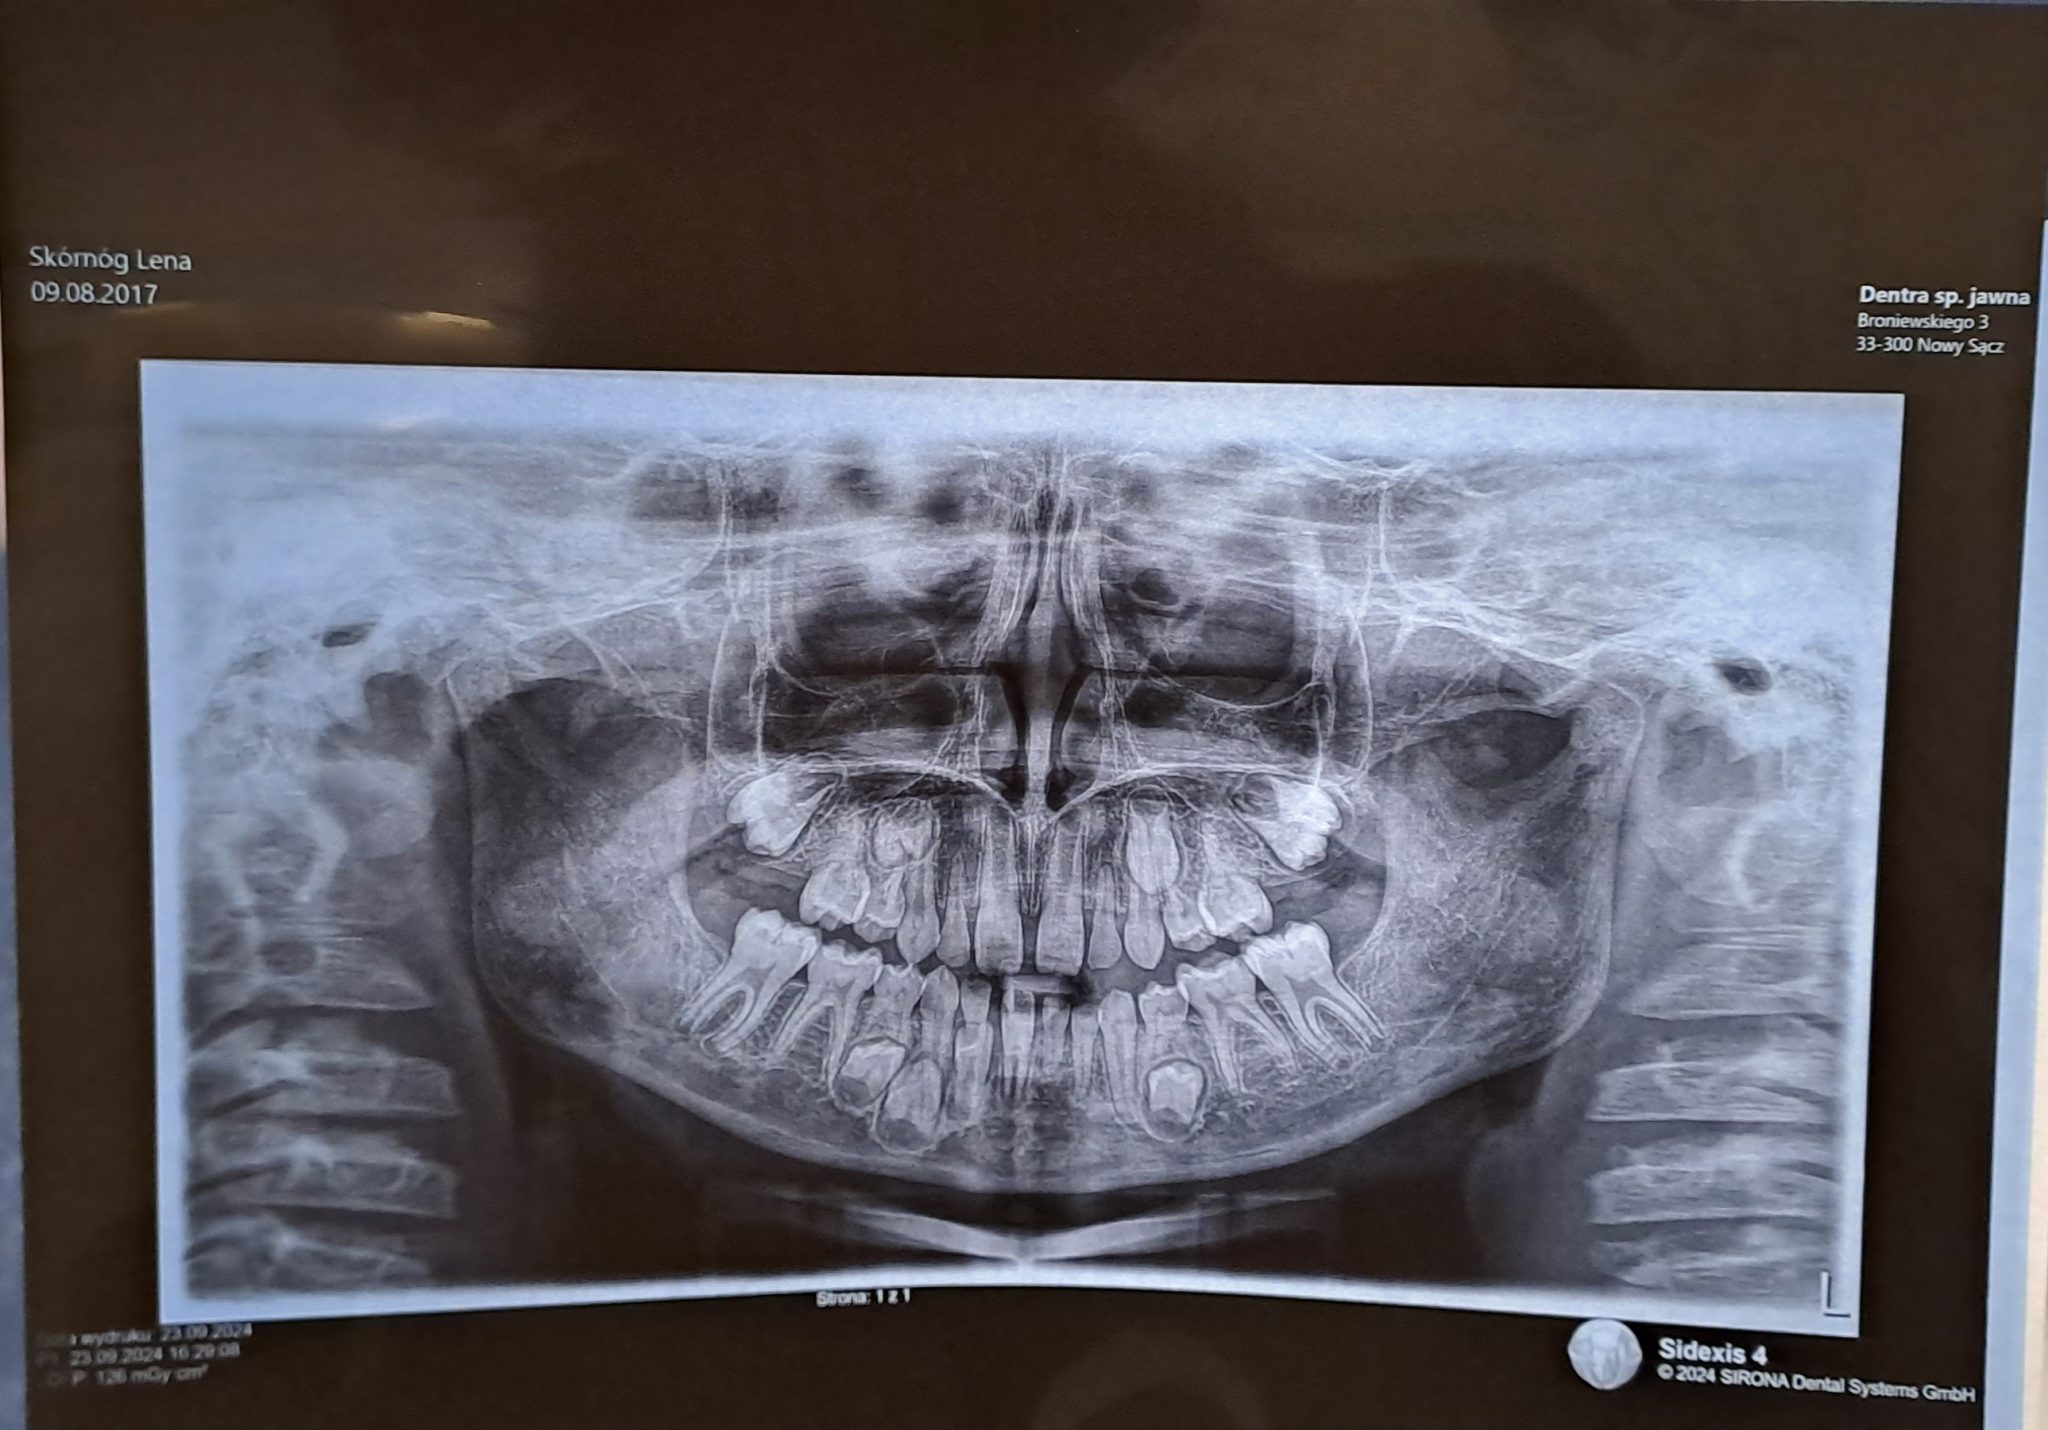

Zwracamy się do Was z niezwykle ważną i osobistą prośbą. Nasza 7- letnia córka Lenka zmaga się z bardzo rzadką wadą zwaną OLIGODONCJĄ.

Oligodoncja to wada charakteryzująca się brakiem zalążków zębów stałych, u Lenki brakuje aż 15 zalążków. Przed Lenką niełatwa dla dziecka droga. Czeka ją leczenie stomatologiczne, ortodontyczne, protetyczne, chirurgiczne i dopiero na samym końcu, gdy wysokość kości będzie odpowiednia leczenie implantologiczne. Całe leczenie wiąże się z ogromnymi kosztami. Samo leczenie implantologiczne to koszt ponad 70 tysięcy. Niestety leczenie implantologiczne nie jest refundowane, a dodatkowo tak rzadką wadę leczy się w największych miastach w Polsce, co wiąże się dla nas z kosztami dojazdu.